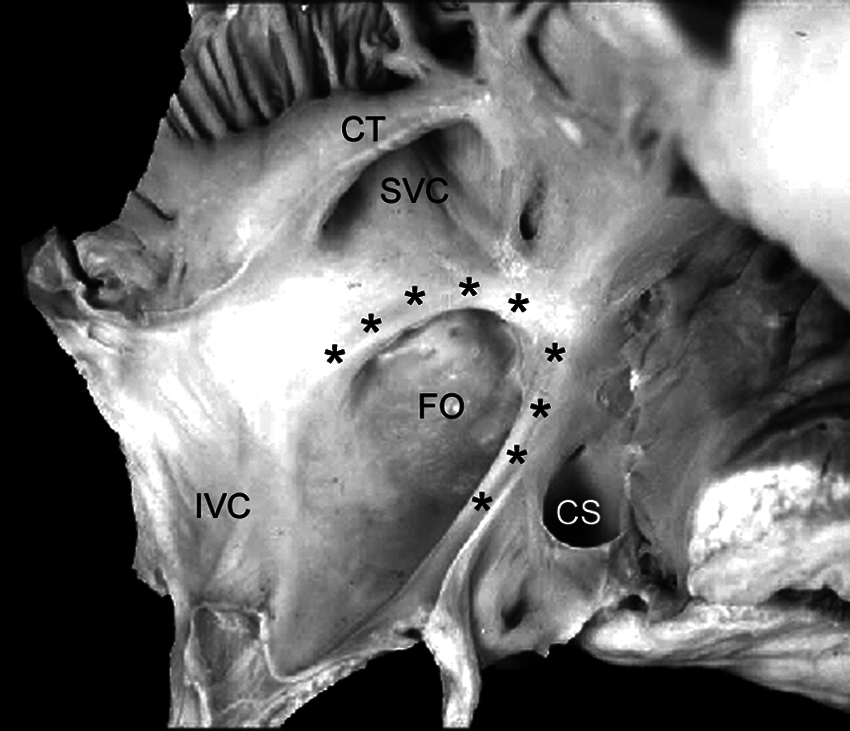

Figure 1: Specimen photograph showing normal atrial septum seen from the right atrial side. The party wall between the two atria consists of the floor of the fossa ovalis (FO) surrounded by the limbus (asterisks) that is imperceptibly continuous with the free wall of the atria and the walls of the draining veins. The limbus is poorly formed posterior-inferiorly toward the inferior vena cava (IVC) with the floor of the fossa ovalis appearing to be an interatrial continuation of the inferior vena caval wall. CT, crista terminalis; CS, coronary sinus; SVC, superior vena cava